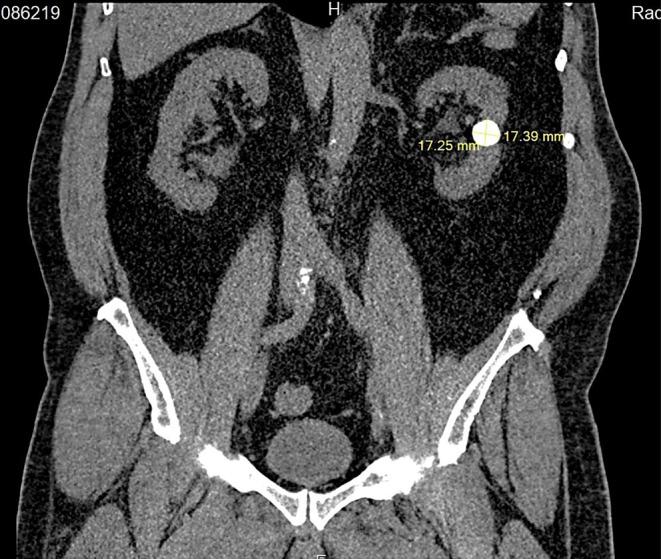

This study aims to present a case of laparoscopic nephrolithotomy and highlight its successful outcome. The patient was a 65-year-old male who experienced intermittent colicky flank pain. Imaging revealed the presence of a 20-mm round-shaped stone in a hydronephrotic calyx located in the mid-pole of the left kidney, possibly with a parenchymal component. Given the stone's location, neither percutaneous nephrolithotripsy (PCNL) nor ureterorenoscopy (URS) was considered feasible. The findings of this study demonstrate the effectiveness and suitability of laparoscopic nephrolithotomy (LNL) in managing stones. It emphasizes that LNL can be utilized not only as an alternative treatment but also as a viable initial option when appropriate case selection is made.

本研究旨在介绍一例腹腔镜肾切开取石术病例,并突出其成功结果。患者为一名65岁男性,经历间歇性绞痛性胁腹疼痛。影像学检查显示,在左肾中极肾积水的肾盏中有一个20毫米圆形结石,可能伴有实质成分。鉴于结石的位置,经皮肾镜取石术(PCNL)和输尿管肾镜检查(URS)均被认为不可行。本研究结果证明了腹腔镜肾切开取石术(LNL)在处理结石方面的有效性和适用性。它强调,当进行适当的病例选择时,LNL不仅可以作为一种替代治疗方法,而且可以作为一种可行的初始选择。